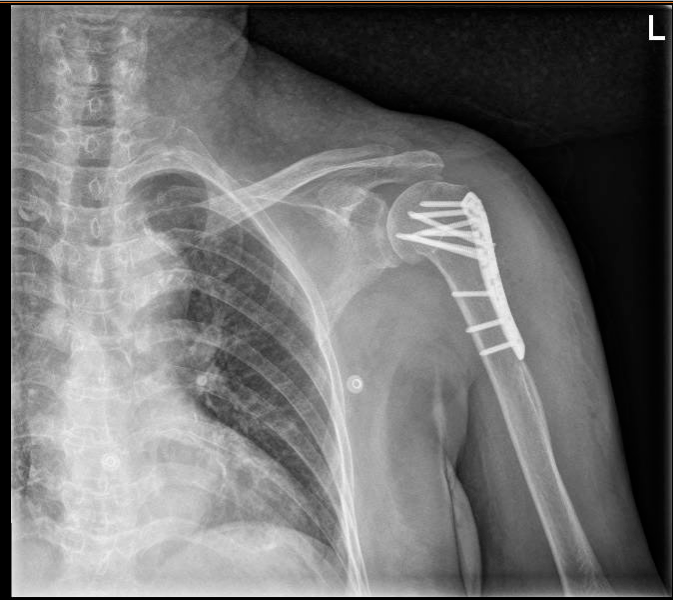

【治疗|精准评估,多学科诊疗护佑老年患者健康】今年7月底 , 李大娘因为左肱骨骨折再次入住骨科 , 准备行切开内固定术 , 在术前评估中主管医生张大夫眉头紧锁:李大娘的心电图较过去2年不一样了 , 立刻申请了心内科会诊 , 经过详细研读检查材料 , 仔细询问病史 , 会诊医生刘大夫发现李大娘心电图II、III、aVF导联较2年前新出现了Q波 。 这也提示着 , 李大娘在过去2年间出现过心脏下壁心肌梗死!

之后 , 李大娘转回骨科并接受了左肱骨切开内固定术 , 手术很成功 。